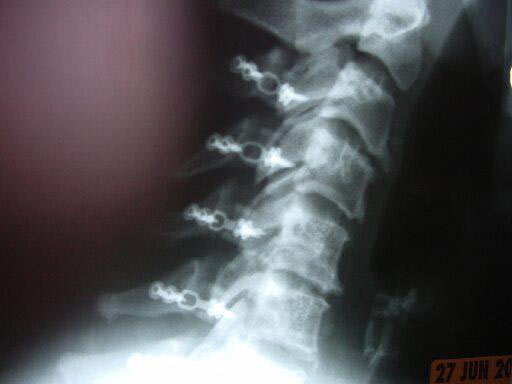

63 -year- old female with multilevel cervical myelopathy and stenosis.

The system uses pre-bent miniplates that are designed to follow the anatomy of the cervical spine. The miniplates are longer on the lamina and shorter on the lateral mass. A slot on the miniplate allows a screw to hold the graft in position and eliminates its migration towards the spinal cord.

The system features 2.0 mm self-drilling and self-tapping screws as well as 2.4 mm rescue screws.